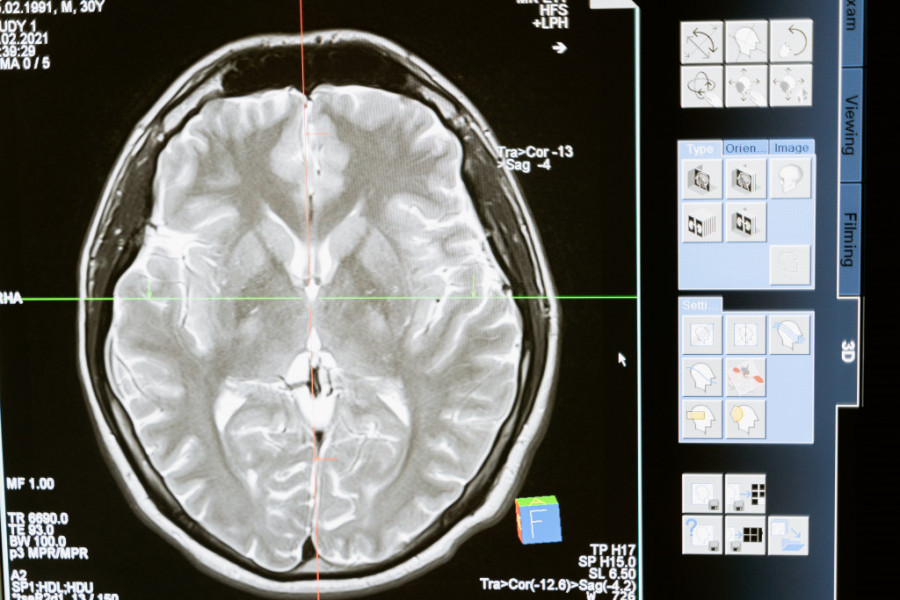

CT i MRI snimci otkrili su prisustvo cisti u mozgu, a dijagnoza je bila neurocisticerkoza, parazitska infekcija koja može nastati konzumiranjem zaraženog mesa. Lekari veruju da je parazit ušao u telo pacijenta nakon konzumiranja nedovoljno pečene slanine i putovao iz creva do mozga krvotokom, piše "Miror".